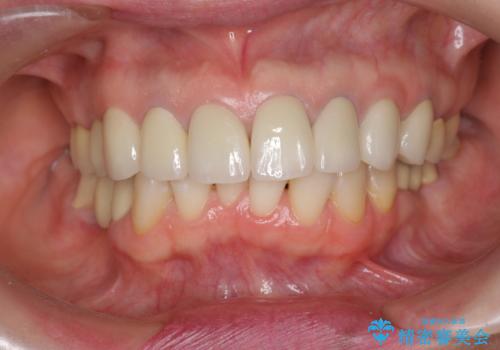

前歯の突き上げを改善する インビザライン による小矯正

- 下顎前歯のガタつきにより上顎前歯のクラウンに突き上げ・動揺が認められ、また歯ぎしりもあることから下顎前歯のみの小矯正をインビザライン で行うこととなりました。